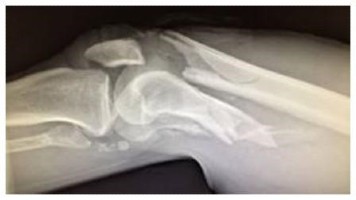

Fracture comminutive du tibia-péroné (radiographie de la cheville en latéral).